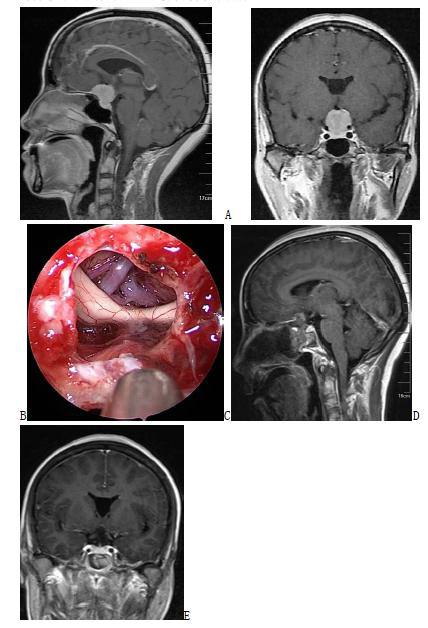

图3. 六例实性侵袭第三脑室颅咽管瘤手术前、后的增强磁共振影像以及手术中截图,提示肿瘤全部切除,可以看到第三脑室后壁、室间孔和中脑导水管上口。